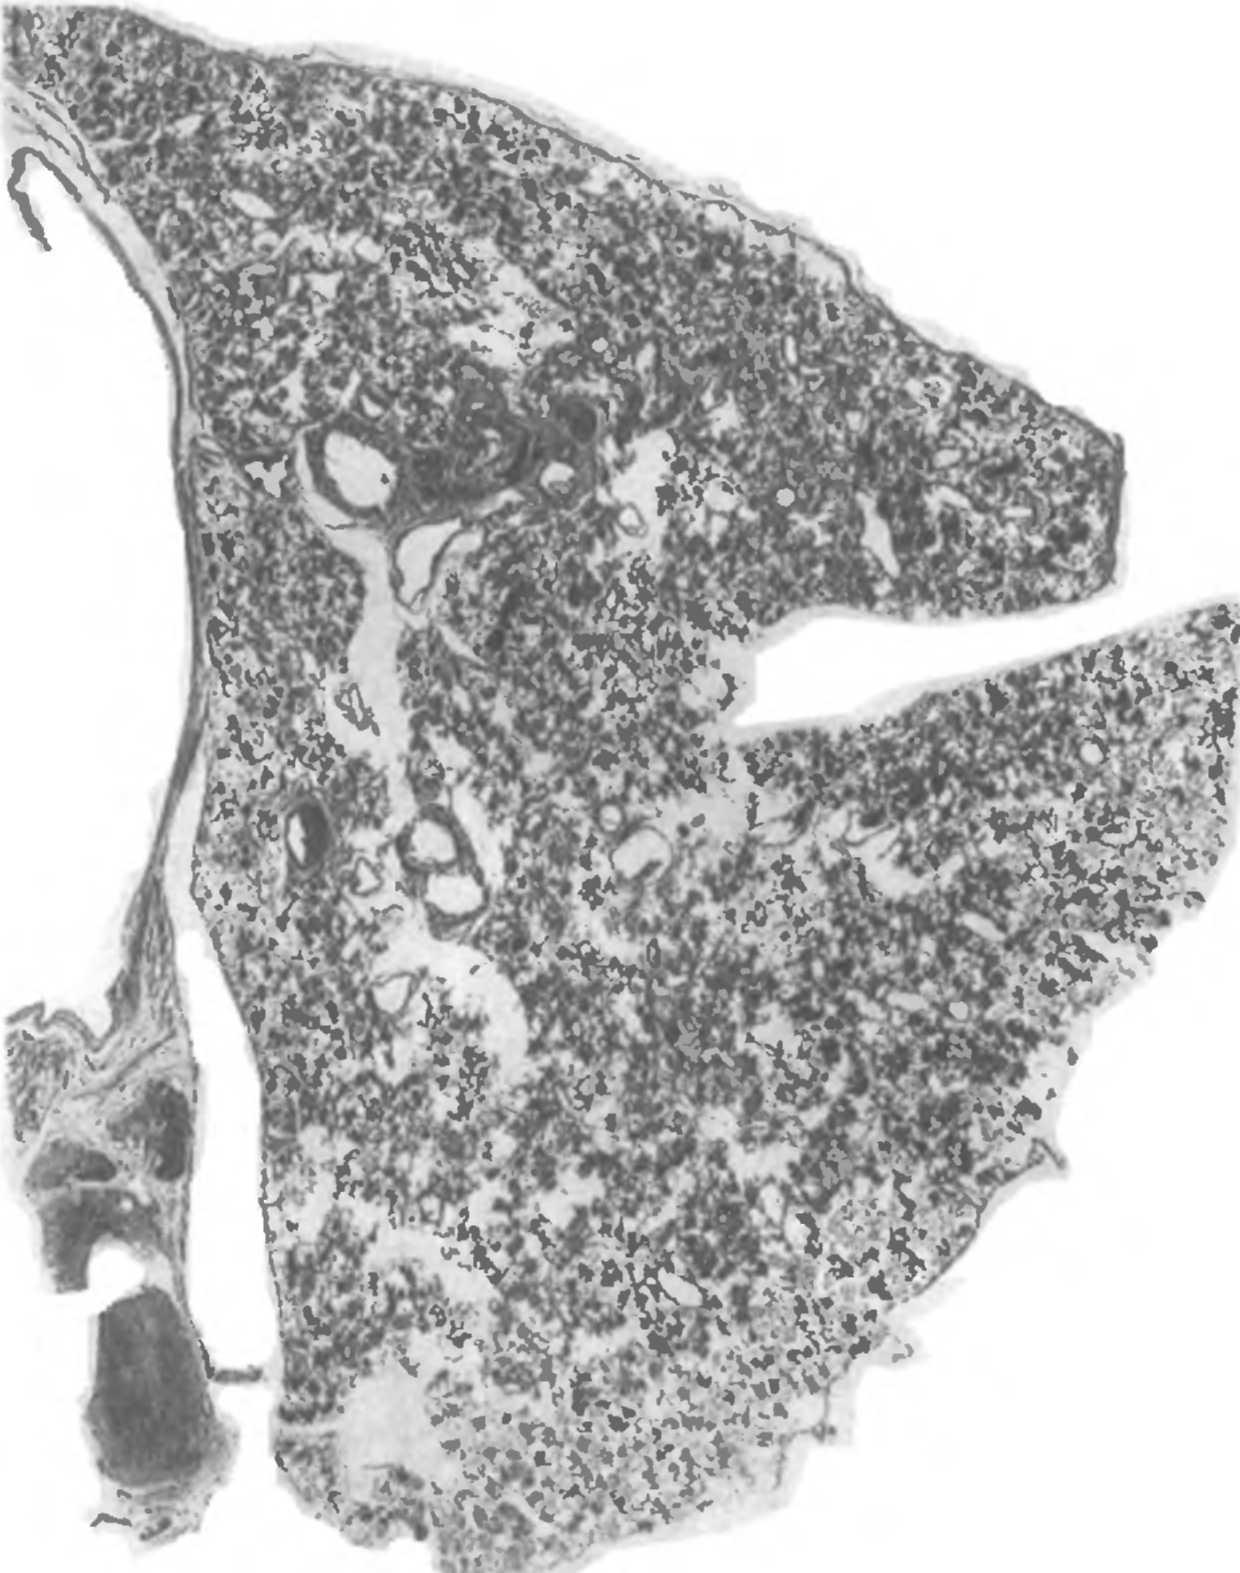

Микроскопический взгляд на мишитарный туберкулез легкого: фотодокументация

/Kozmina.files/image004.jpg)

Раздел: Снимки-откровения